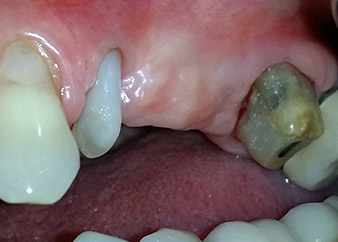

A 58-year-old female patient complained of pain and increased mobility of her bridge abutment tooth 24. Periodontal inflammation was present with pocket depths of 7 mm mesiobuccally and more than 12 mm distally, as well as third-degree furcation involvement. Moreover, the radiograph revealed an extensive periodontal lesion around the apical region of the (alio loco) endodontically pretreated tooth 24 (Fig. 1).

One year earlier, teeth 25 and 26 had been extracted due to trauma and for endo-perio reasons, prior to the placement of the bridge. A combined endo-perio lesion was diagnosed for tooth 24, of unclear aetiology. The patient wanted to keep her bridge abutment teeth 24 and 27 and would not accept a final, or even temporary, removable prosthesis. Therefore, it was agreed to make all efforts to retain both teeth, in spite of their poor prognosis as based on radiological and clinical findings.

Placement of two submerged implants was planned at sites 25 and 26, in a surgical session with open periodontal debridement and apicoectomy of tooth 24. Due to the vertical bone deficiency at the future implant site, an internal sinus augmentation was also planned.